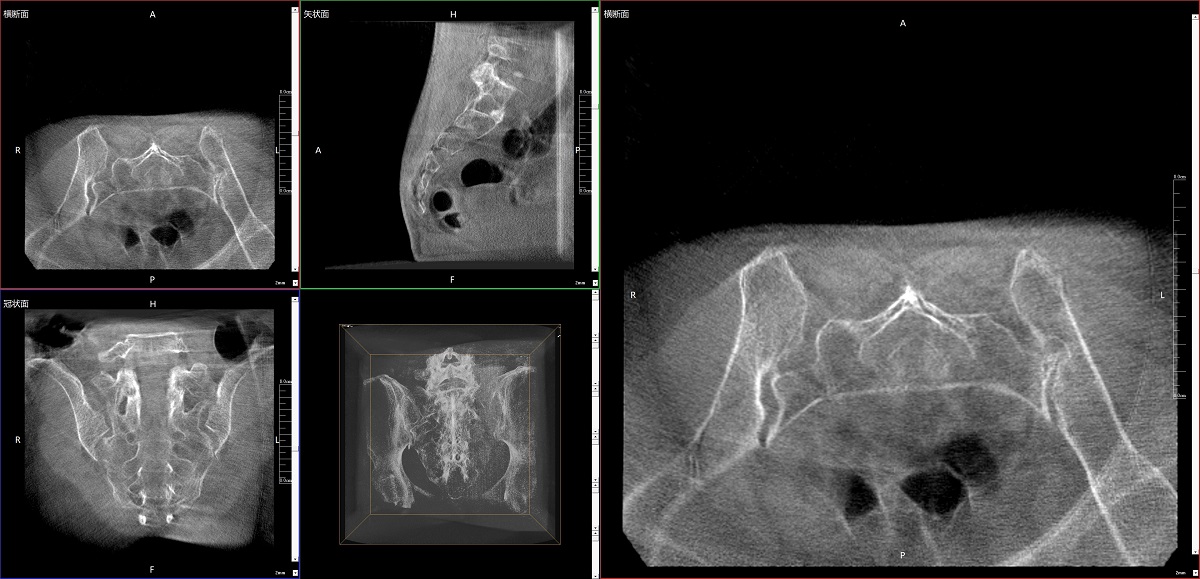

在骨科手術(shù)中,影像相當(dāng)于醫(yī)生的“眼睛”,要先“看得清",才能“算得準(zhǔn)” “打得穩(wěn)”。普愛醫(yī)療第三代平板三維C形臂協(xié)同醫(yī)院創(chuàng)傷導(dǎo)航機器人已開展多例“骨盆骨折微創(chuàng)手術(shù)”,成為上海市第七人民醫(yī)院手術(shù)技術(shù)創(chuàng)新的一大亮點。

普愛醫(yī)療第三代平板三維C形臂出色的二維透視和術(shù)中三維成像效果,為機器人提供了精確的術(shù)中影像依據(jù),協(xié)同提升手術(shù)整體的精準(zhǔn)度和效率,為患者帶來了更安全、更高效的醫(yī)療服務(wù)體驗。